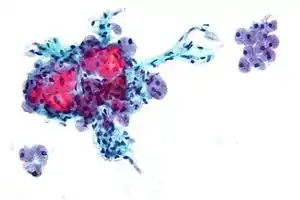

| Micrograph showing Hürthle cells in a Hürthle cell neoplasm. Pap stain. | |

Hürthle cells arise from the follicular epithelium. Key features of these oncocytic cells include a granular cytoplasm that stains eosinophilic (pink on H&E stain) and a vesicular nucleus with a large nucleolus.[6] A Hürthle cell is larger than a follicular cell, and its cellular material stains eosinophilic. Hürthle cells also tend to be large, polygonal cells with distinct cell borders.[4] The cytoplasm of the oncocytes in Hürthle cell adenomas and carcinomas is characterized by an eosinophilic granular nature, which is commonly due to the oncocytes' high content of mitochondria.[6] Some of these cells can contain up to 5,000 mitochondria, which fills the cytoplasm to the point of nearly excluding other organelles.[4] This high amount of mitochondria is reported to be a result of mutations in the mitochondrial DNA.[4] Some scientists have identified these mutations as deletions in the mitochondrial DNA of Hürthle cells found in neoplasms and Hashimoto's thyroiditis.[7]

- ↑ Image by Mikael Häggström, MD. References for findings:

- Ayana Suzuki, C.T., Andrey Bychkov, M.D., Ph.D. "Hürthle cell neoplasm". Pathology Outlines.{{cite web}}: CS1 maint: multiple names: authors list (link) Last author update: 7 May 2020. Last staff update: 12 May 2022

- Shawky M, Sakr M (2016). "Hurthle Cell Lesion: Controversies, Challenges, and Debates". Indian J Surg. 78 (1): 41–8. doi:10.1007/s12262-015-1381-x. PMC 4848220. PMID 27186039. - 1 2 3 4 5 6 7 8 9 10 11 12 13 Schwab, M. (2011). Encyclopedia of Cancer. Encyclopedia of Cancer. doi:10.1016/B0-12-227555-1/00151-9